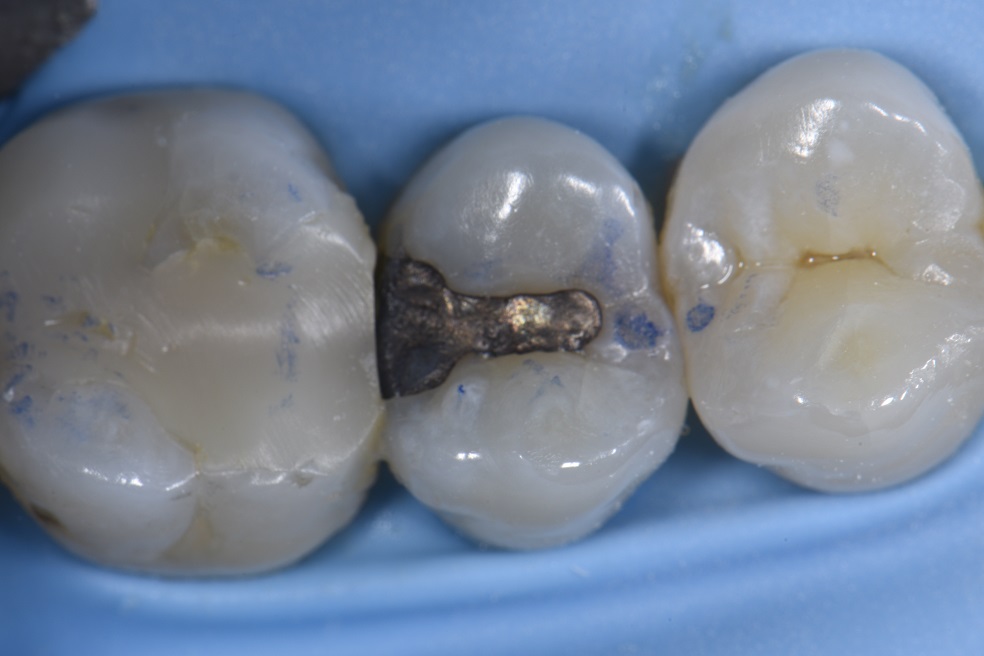

Clinical Case by Dr. Max Andrup Amalgam replacement using an

Clinical Case by Dr. Max Andrup Amalgam replacement using an Composite Resins And Dental Amalgam this health technology assessment (hta) aims to inform the policy question through a comparative assessment of dental. composite resin is the most common alternative to dental amalgam; Although data indicate that rates of restoration failure. — dental composite resin materials are an aesthetic alternative to amalgam, and their mechanical properties. — dental resin composites have revolutionized. Composite Resins And Dental Amalgam.

From www.kuraraynoritake.eu